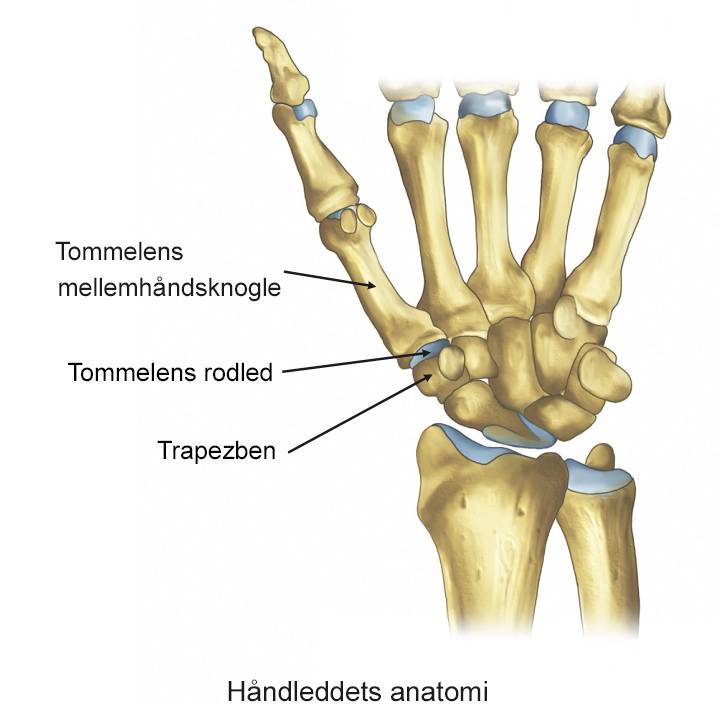

Ved slidgigt i tommelfingeren nedbrydes brusken i tommelfingerens rodled gradvist. Når brusken forsvinder, begynder knoglerne at skurre mod hinanden, hvilket giver smerter, nedsat bevægelighed og nedsat kraft i hånden.

Tommelfingerens rodled sidder ved håndleddets bøjefure og forbinder tommelfingerens mellemhåndsknogle med trapezbenet. Leddet belastes meget under daglig brug, og da leddet samtidig er meget bevægeligt, bliver det sårbart.